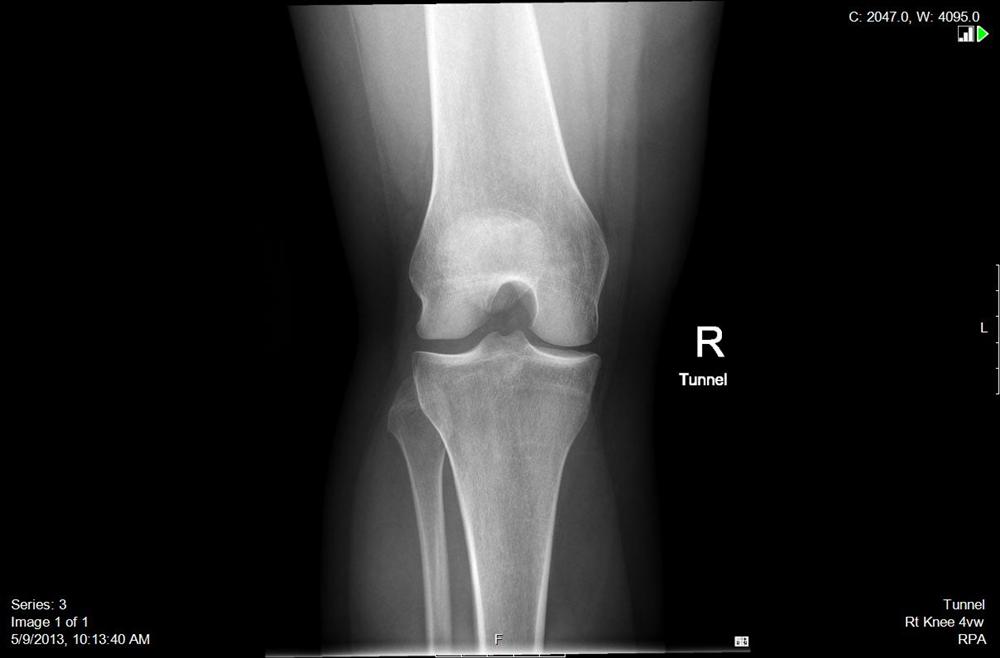

Standing Tunnel Knee X-Ray . Normal knee radiographs with tunnel view on radiopaedia.org. Pa axial projection tunnel view of the intercondylar fossa (knee xray) can be taken in two radiographic method with different patient position depending on patients. Radiographs provide useful information across the entire spectrum of knee pathology, including congenital deformities, arthritis, trauma, oncology, sports injuries, metabolic disease, and arthroplasty evaluation. This view demonstrates the distal femur and proximal tibia/fibula in their natural anatomical position allowing for assessment of suspected dislocations,. Open intercondylar fossa is visualized to enable detection of loose bodies (joint mice). Posteroinferior surface of the femoral condyle is seen.